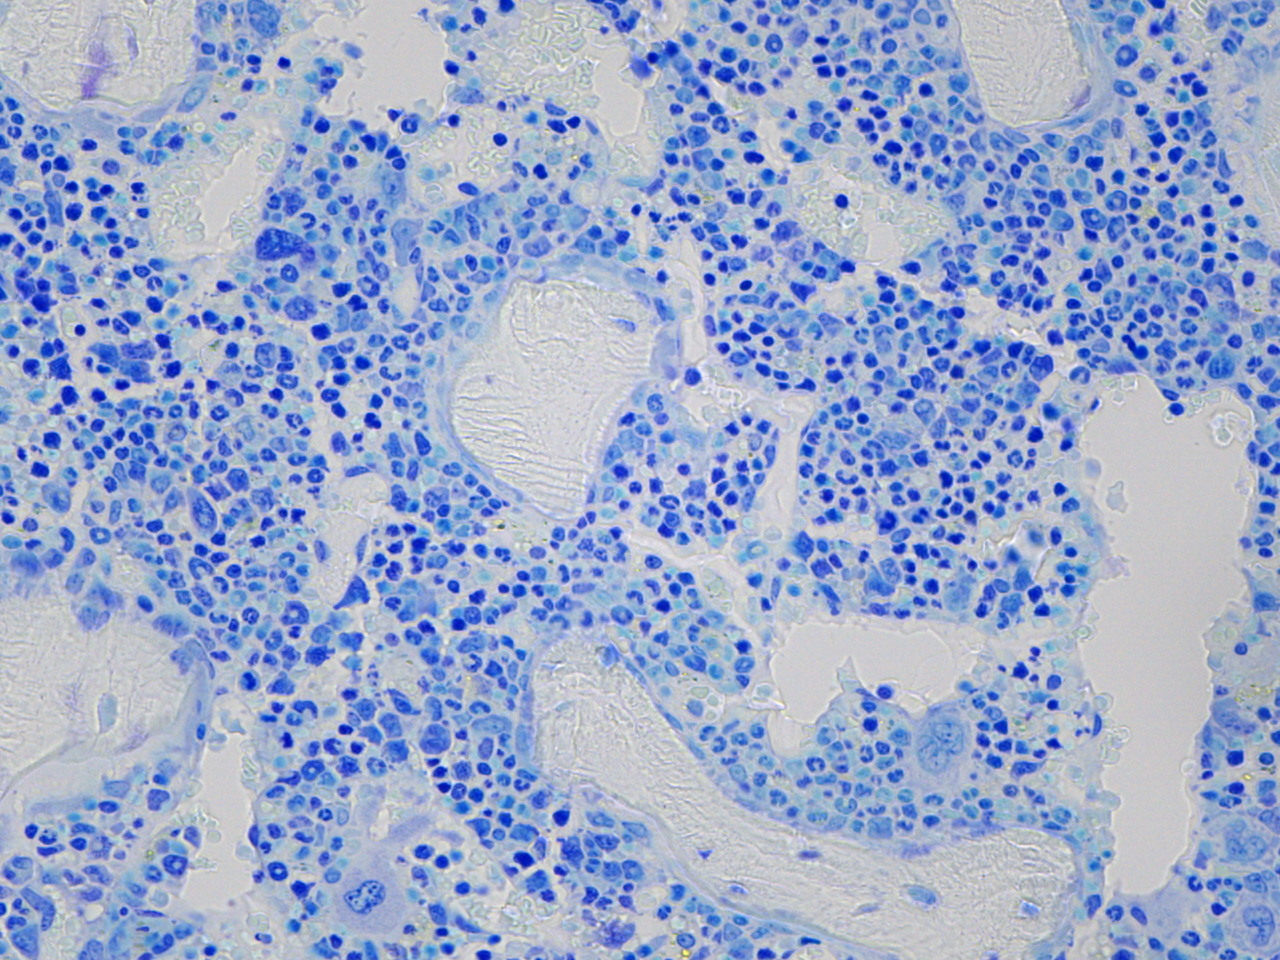

The MD Anderson Bone Histomorphometry Core Laboratory provides histomorphometric analyses of non-decalcified bone specimens. Bone specimens are processed for histology and can be stained for static and dynamic histomorphometric analyses (Osteomeasure or the Bioquant Osteo II system). The core can provides slides, data, training

Research Histology Core Lab: Bone Processing, Embedding and Sectioning

Bone Histomorphometry Core: Staining and Analysis